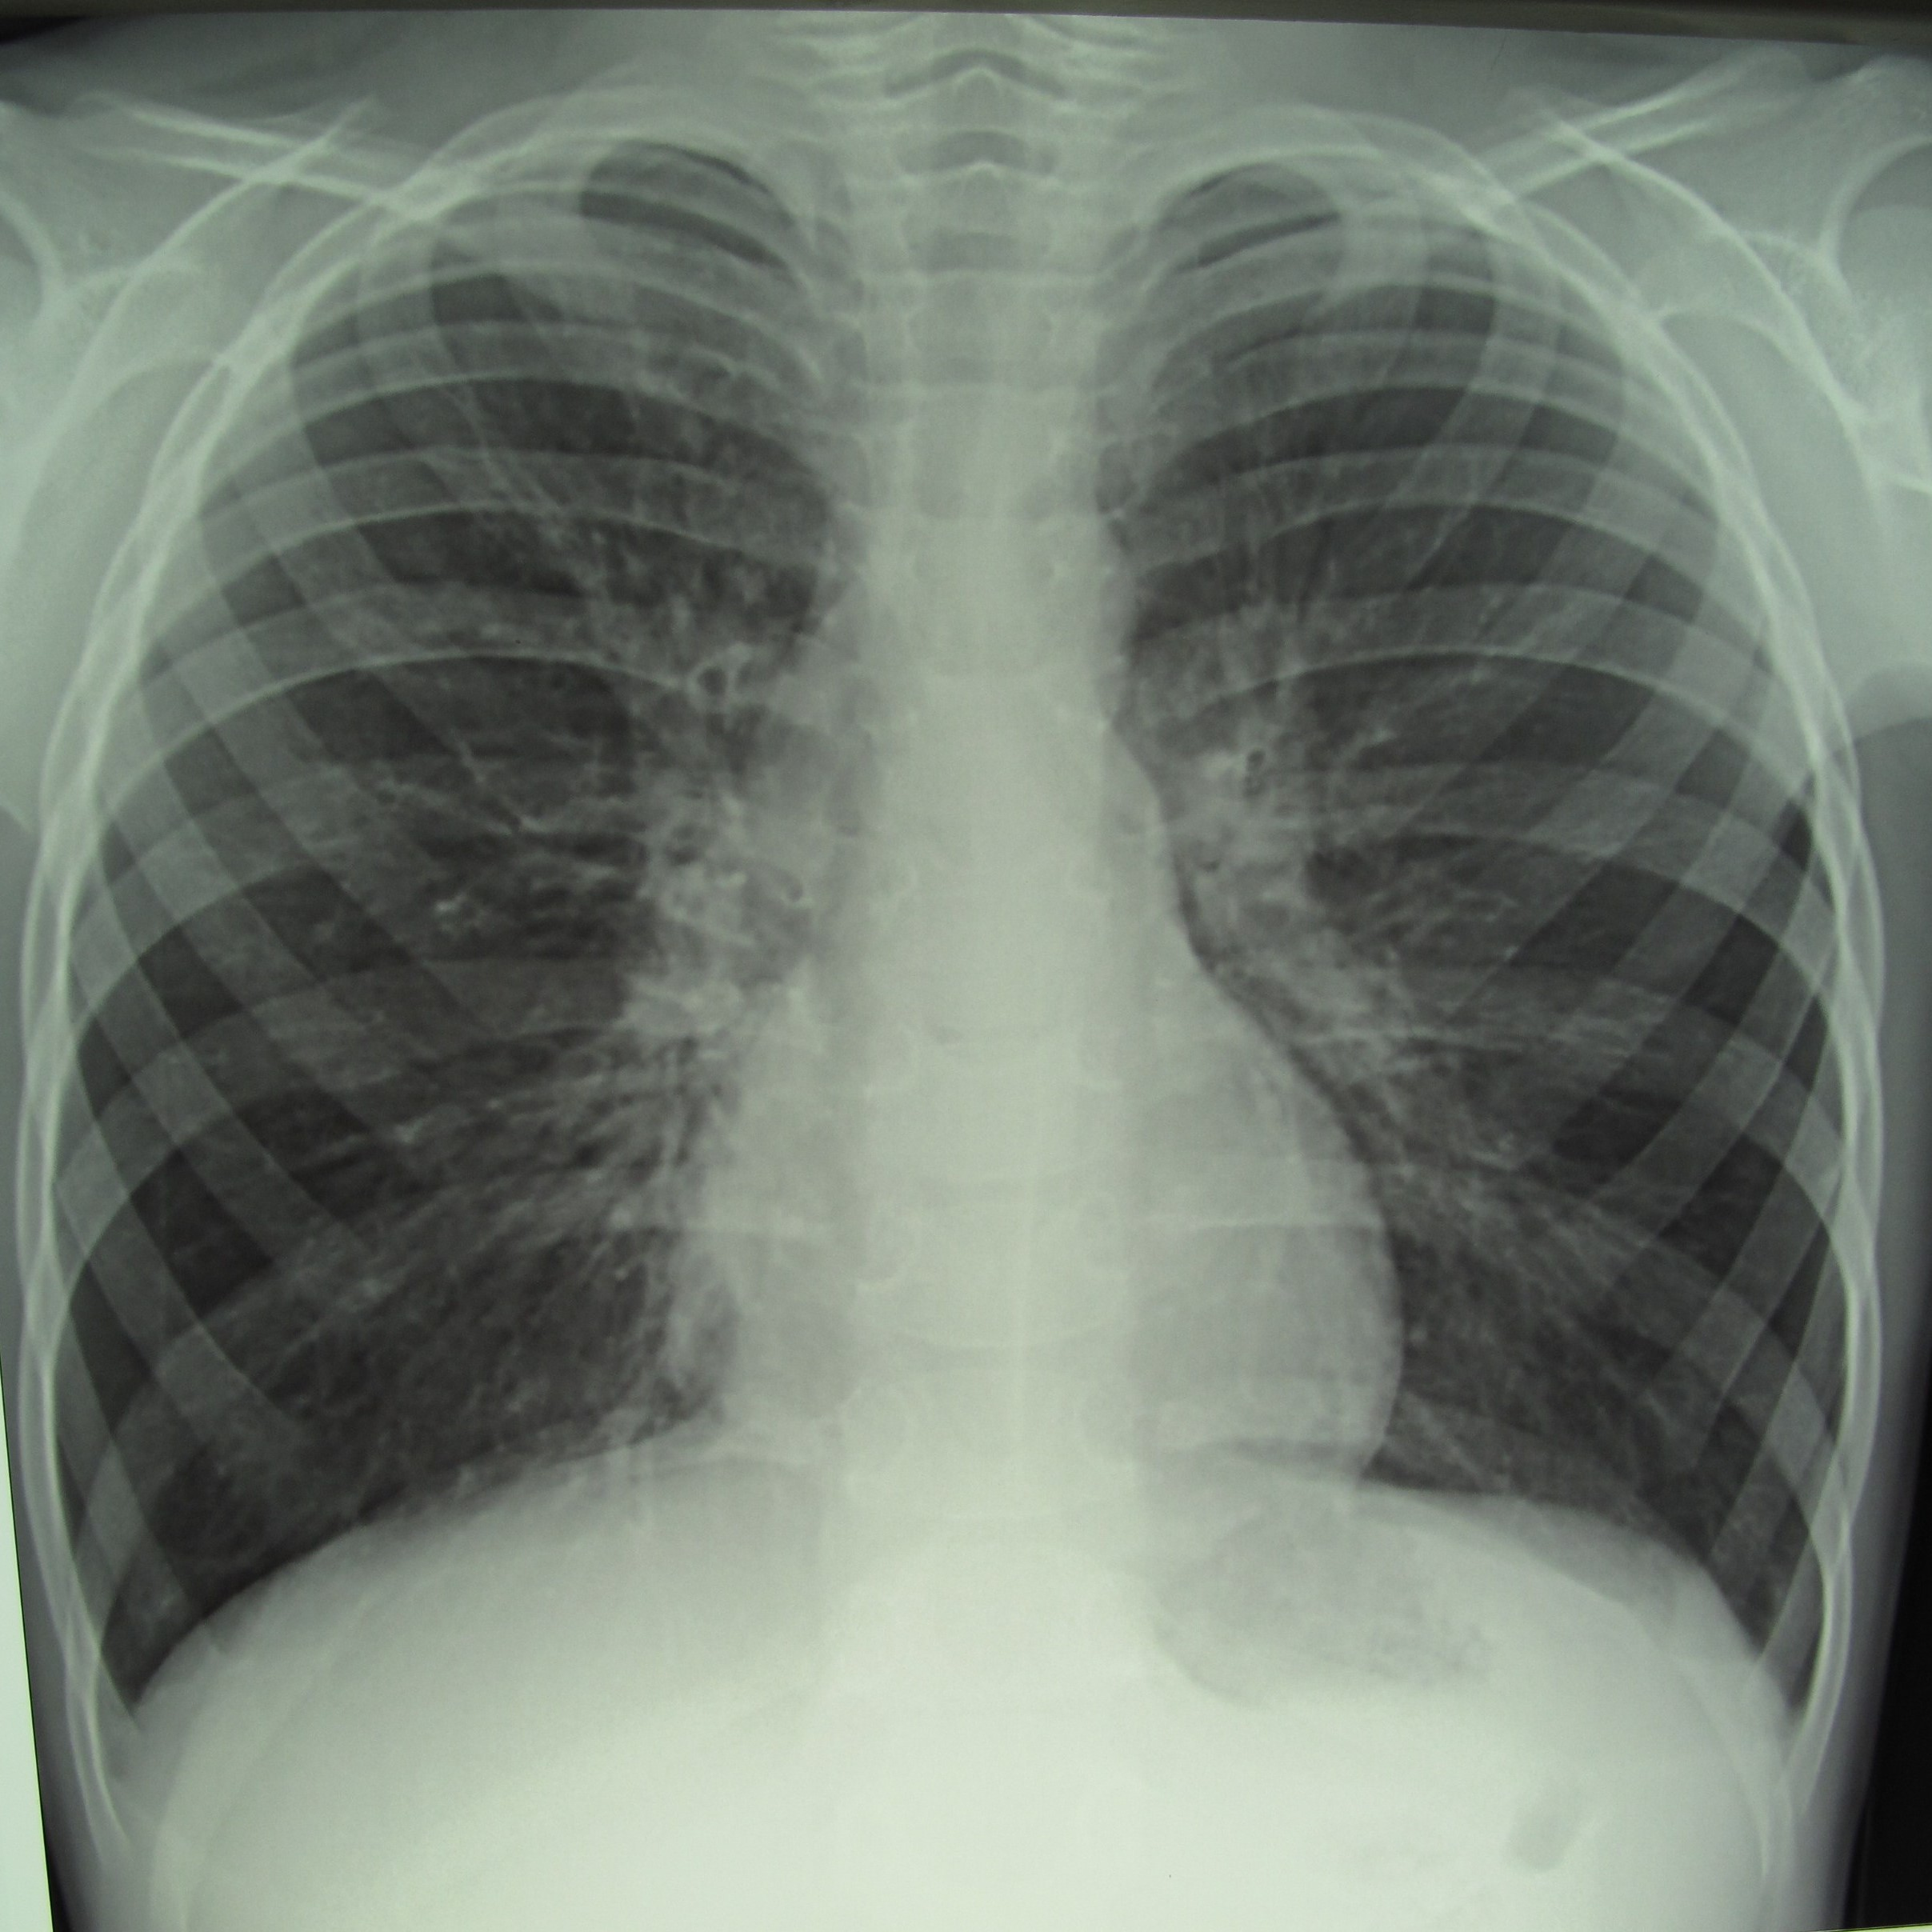

Хрип при прослушивании